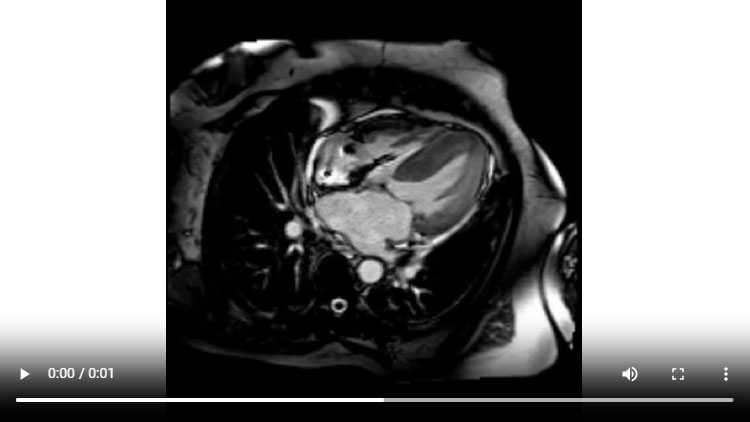

Figure 1C : Séquence Ciné-IRM - Coupes petit-axe apical

Figure 1D : Séquence Ciné-IRM - Coupes 2-cavités

Figure 1E : Séquence Ciné-IRM - Coupes 3-cavités

Figure 1F : Séquence Ciné-IRM - Coupes 4-cavités

- Présence d’une hypertrophie ventriculaire gauche (HVG) asymétrique à prédominance septale mesurée au maximum à 23 mm.

- Visualisation de la sonde de PM avec artéfacts métalliques modérés au niveau du ventricule droit (flèches roses).

- Présence d’un épanchement péricardique de moyenne abondance (flèches rouges).